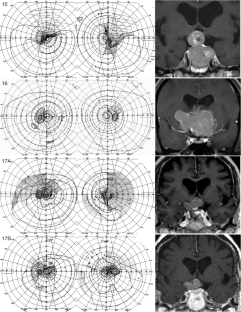

The hemi-decussation at the optic chiasm creates the potential for crossed and uncrossed fibers to be affected in isolation or in various combinations of nerve, chiasm and tract, with patterns that reflect the retinotopic arrangement of axons. We present seventeen cases that illustrate the field defects that can result and review the literature to create a taxonomy of junctional visual field defects. The complete junction defect is blindness in one eye and loss of the entire temporal field of the other. The classic junctional scotoma combines optic neuropathy in one eye with upper temporal hemifield loss in the other, and is often a sign of ventral compression. The less frequent atypical junctional scotoma involves the lower temporal hemifield and has a higher frequency of dorsal compression or non-compressive pathology. There are the monocular defects in the temporal (‘junctional scotoma of Traquair’) or nasal hemifield, the latter of which is rarely if ever due to a pituitary adenoma. Highly asymmetric bitemporal defects with or without a central scotoma and the paradoxical junctional scotoma occur by extension of the lesion causing the junctional scotoma of Traquair. The posterior junction defect results from combined damage to the optic chiasm and optic tract. Recognizing these various patterns is important clinically as junctional defects have the same localizing significance as bitemporal defects and are being encountered more often. In addition the probability of certain types of pathology varies with the type of junctional defect.

Figures in cases 1, 6 and 12 are adapted with permission from: Barton JJS, Benatar M. Field of Vision: a manual and atlas of perimetry, Humana Press (now Springer Nature), Totowa NJ, 2003, and those of cases 7, 9 and 15 are reproduced with permission from www.neuro-ophthalmology.ca. We thank Briar Sexton for sharing case 9 with us.